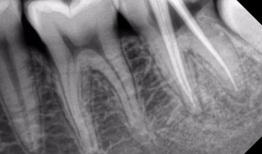

最近是不是牙齿疼得你坐立不安,连笑容都变得苦涩了呢?别担心,今天就来给你揭秘一下那个听起来有点吓人的根管治疗,让你对这个过程有个...